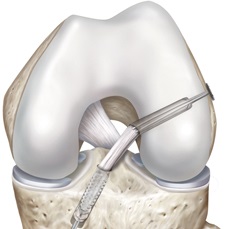

Die Turnweltmeisterschaft im Oktober in Nanning / China sollte jetzt der Höhepunkt werden. Im August dann die Verletzung: eine kombinierte Kapsel-Sehnenverletzung in der Kniekehle nach einer Landung beim Dreifachsalto.

Was tun? Eine Operation oder eine Ruhigstellung hätten die Teilnahme an der WM unmöglich gemacht. Abljasin entschied sich schließlich zu einer konservativen Behandlung in München bei Dr. Kinateder, Kniespezialist im ZFOS, und Cyrus Salehi, Chef–Pysiotherapeut des DTB und Leiter des Consports-Centers. Der Therapie- und Trainingsplan wurde eng abgestimmt mit den Trainern des russischen Turner-Teams. Es war ein guter Plan, wie sich zeigte. Denis Abljasin wurde überraschend Weltmeister am Boden. Mit perfekt gestandenem Dreifachsalto. Zudem wurde er Dritter an den Ringen.